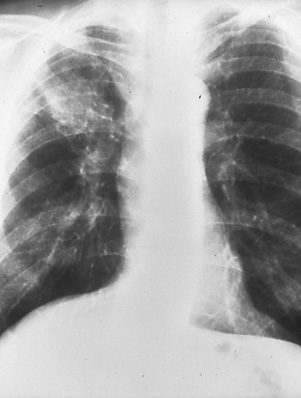

Fig. 25a & b: a) Posterior-anterior chest radiograph shows a mass with irregular borders and infiltrate in the right upper lobe. b) Computed tomographic scan of the chest delineates the right upper lobe mass and enlarged lower paratracheal nodes (white arrow), N2 disease.